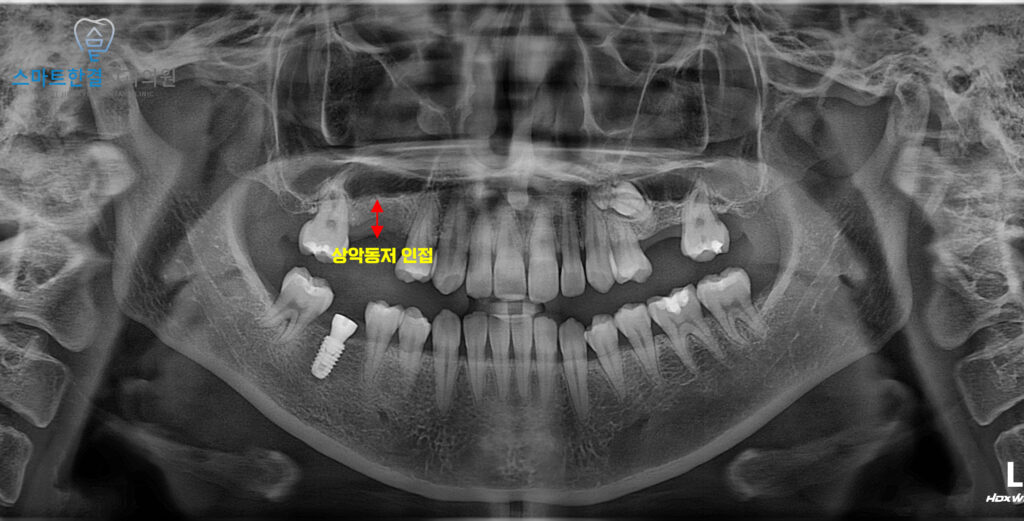

25.01.22

이렇게 두 치아를 발치했어요.

해당 부위는 치아 두 개가 연속으로 빠지면서

결손 범위가 비교적 컸고,

위쪽 어금니 부위 특성상 상악동저와

매우 가까운 위치에 있었어요.

이로 인해 잇몸뼈의 높이가

충분하지 않은 상태였으며,

바로 임플란트를 식립하기에는

안정성이 떨어질 수 있는

상황이었어요.

25.09.06

이렇게 어느정도의 잇몸이 회복된 후

임플란트 식립을 진행했어요.

먼저 잇몸뼈의 가장 위쪽인

치조정 부위로 접근하여,

상악동 안쪽에 있는 얇은 막을

조심스럽게 들어 올리는

상악동 거상술을 시행했답니다.

이 과정을 통해 임플란트를

심을 수 있는 공간을 확보한 뒤,

충분한 지지력을 얻을 수 있도록

임플란트를 안정적으로 식립했어요.

25.01.22 / 25.09.06

화서동치과 스마트한결치과의

임플란트 수술 전후 사진이에요.